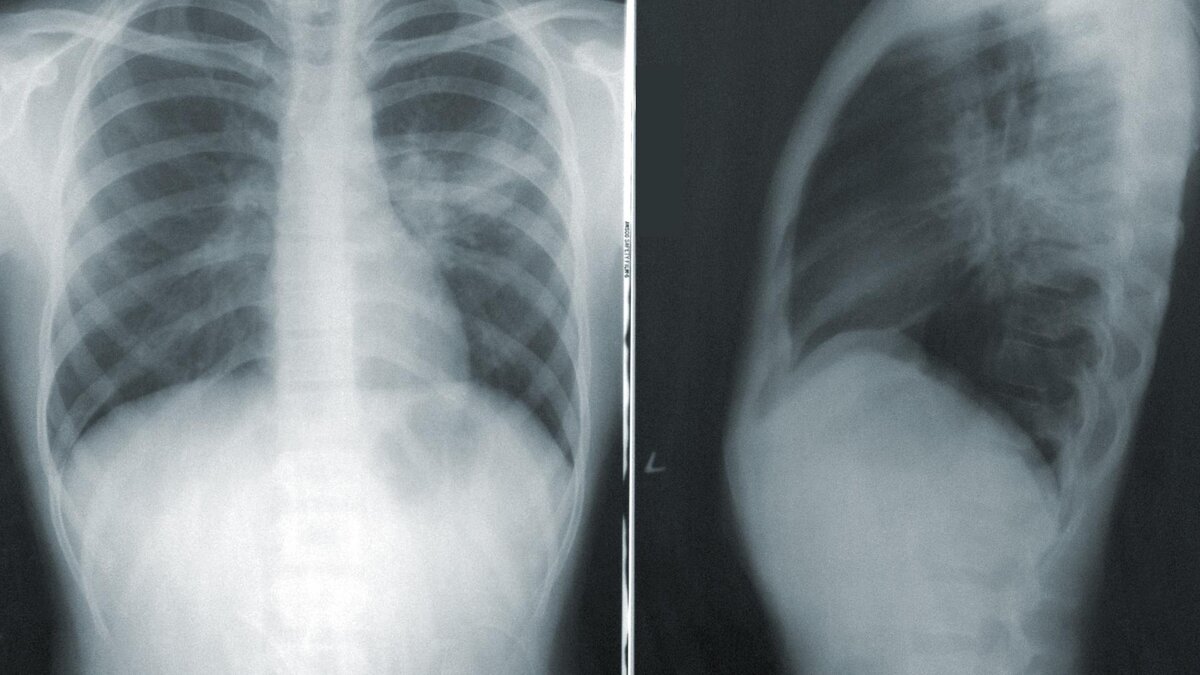

• Рентгенограмма грудной клетки. Это позволяет врачу определить локализацию воспаления легких.

Внебольничная пневмония — это пневмония, приобретенная за пределами больницы. Чаще всего выявленными возбудителями оказываются пневмококк, атипичные бактерии и вирусы. Среди симптомов — лихорадка, кашель, выделение мокроты, боль в груди, одышка, тахипноэ и тахикардия. Диагноз ставится на основании клинического обследования и рентгенографии органов грудной клетки.